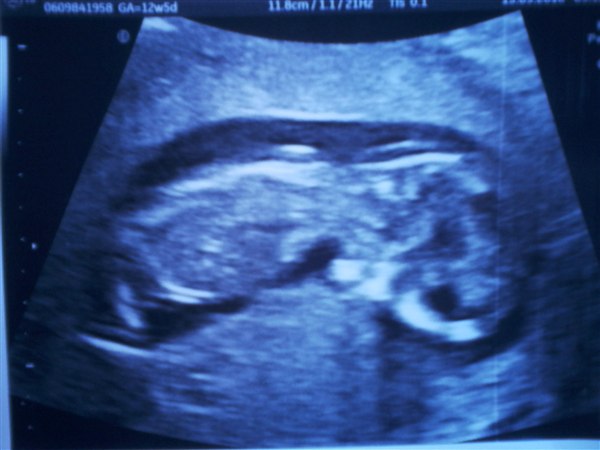

Så er Nf scanningen overstået og ALT var som det skulle være :love:

Vores lille bebse har 2 arme, 2 ben, et lille fint hjerte som slår som det skal, et fint hoved hvor vi kunne se de 2 hjernehalvdele :love:

risikovurderingen blev sat til 1:18300 så det er bare helt perfekt :klap:

Blev rykket fra 12+5 til 13+3

Bebse var dog ikk så fotogen :griner: den lå og kiggede ind i min ryg og ville bestemt ikke vende sige trods flere forsøg :rofl:

Vedhæftede fotos (klik for at se i fuld størrelse)